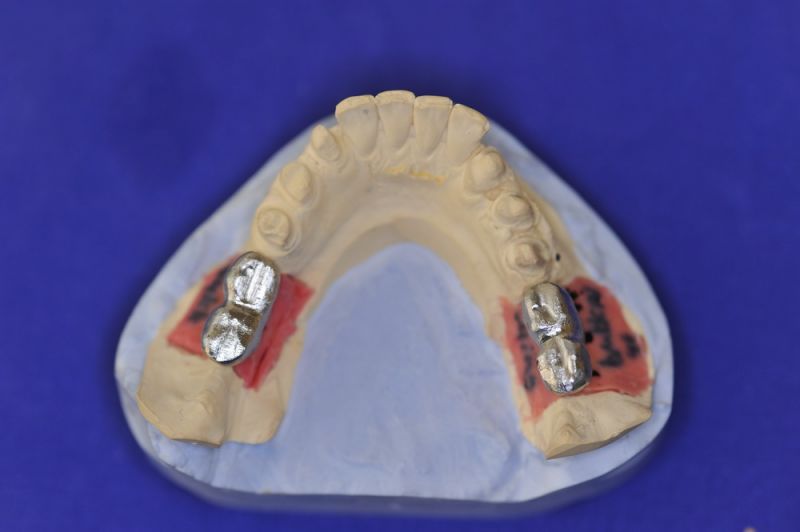

Es war eine Kombination aus Schmerzen bis an die Suizidgrenze, beschränkten wirtschaftlichen Möglichkeiten, sehr stark eingeschränkten Möglichkeiten der für Implantate zur Verfügung stehenden Knochenverhältnisse in einem stark atrophierten Unterkieferseitenzahnbereich und zudem dann auch noch durch auftretenden Problemen bei der Implantatinsertion und nachfolgenden Versorgung der Implantate.

Die Problematik der Implantatversorgungen kann man in einer Analogie folgendermaßen darstellen. Die räumlich beengten Zustände gleichen dem Tanz eines Paares auf einer Briefmarke, und der gleichzeitigen Schritt- und Fusshaltung, dass beim Tanzen die Schuhe geputzt werden können!